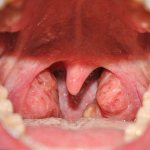

Врач заподозрит опухоль в цервикальном канале по бочкообразной форме шейки, ее гипертрофии и асимметрии наружного зева. Из него может выступать полипозное образование ярко-розового цвета. Оно имеет округлую или гроздевидную форму, мягко-эластичную консистенцию. Если полип вдруг посинел, то, скорее всего, в нем нарушено кровообращение. В дальнейшем это может стать причиной некроза узла.